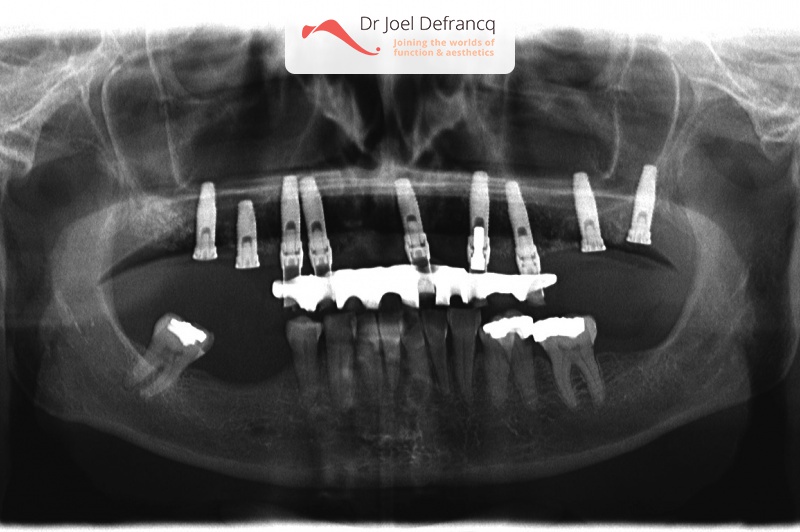

Axelle: new teeth in a week - implants.

Behandeling tandheelkundige implantaten

- Vaste tanden op implantaten (bovenkaak)